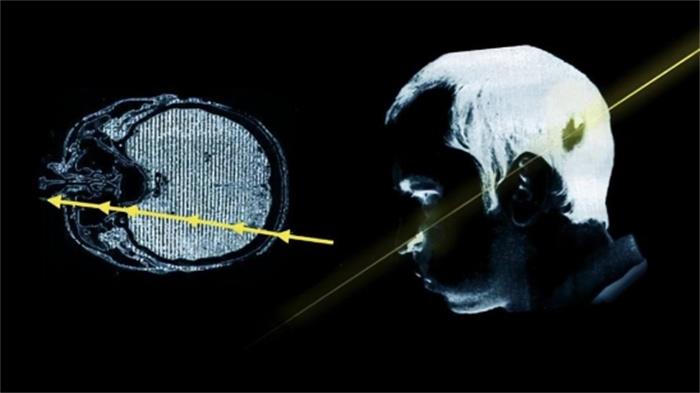

在这位物理学家将头探进去的一刹那,还在管道内以接近光速运行的高能质子束瞬间从他的左后脑穿到了左脸。

这个高能质子束大约包含十的十二次方数量级的高能质子脉冲,其携带的辐射高达20万拉德,从理论上来说,500拉德的辐射就足够使一个成年人致死,所以20万拉德,理论上能让一个人死400回。

据邦格里斯基描述,在质子束打过来的一瞬间,他没有丝毫的疼痛感(可能是因为太快了),只感觉到一瞬间的强烈闪光,然后就什么都不知道了,

等他再醒来时,看见的就是束手无策的医生和自己面目全非的左脸了,这时候大家都以为邦格里斯基将不久于人世,然后住院几周后,他的病情却逐渐稳定了下来,辐射导致的脱发消失了,原本已经失聪的耳朵也逐渐能听到微弱的声音。

只有被轰击的左半边脸无法再控制,成了永久性面瘫,最重要的是,这束贯穿他大脑的质子束没有损伤他的质量,出院不久后他就拿到了博士学位。

邦格里斯基的好运气,后来被归功于质子束的“快准狠”,因为根据后来的研究,轰击他的质子束直径只有10的负15次方米,在穿过邦格里斯基大脑的瞬间,质子束还没来得及释放辐射就又穿过去了,所谓的20万拉德辐射只是看起来吓人,真正作用到邦格里斯基身上的只是一小部分而已。